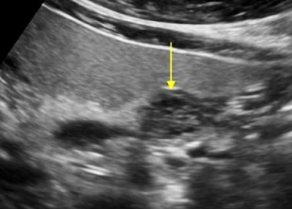

Describe this image

Diagnosis?

Transverse image of pancreas

Pancreatic parenchyma appears hyperechoic with echogenic foci (calcifications) throughout.